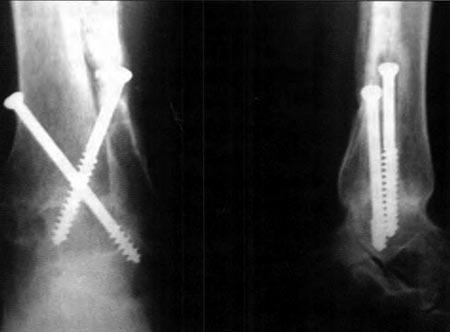

Se utilizaron, en 13 casos, tornillos canulados (Fig 5 a y b) de 7 mm de diámetro con arandelas y la ayuda del intensificador de imágenes para corroborar la posición de los tornillos, evitando que violen la articulación subastragalina. Estos son colocados en forma cruzada, desde la tibia, con dirección posteroanterior hacia el centro del cuerpo del astrágalo, con una angulación de 45° con respecto al eje tibial, realizando compresión entre las superficies cruentadas, ajustando los tornillos en forma alternada. En dos casos en que no se contó con tornillos canulados se utilizó tornillos de esponjosa de 6,5 mm En el caso restante se colocó un tutor externo clásico de Charnley tambien con buen resultado.

Figura 5a: pos. op. frente

Figura 5b: pos. op. perfil

Consolidación 8 semanas